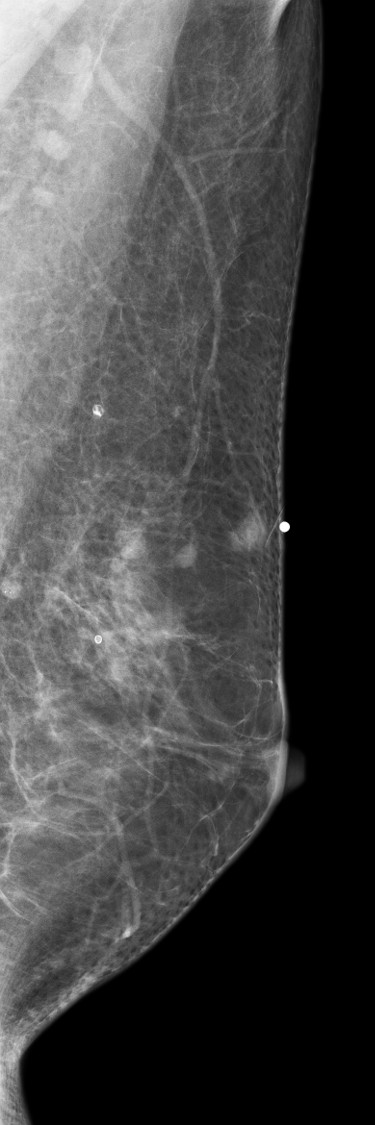

[355,Breast] 61/F,A palpable mass in the left breast

Breast

US,Etc,

What is your diagnosis?